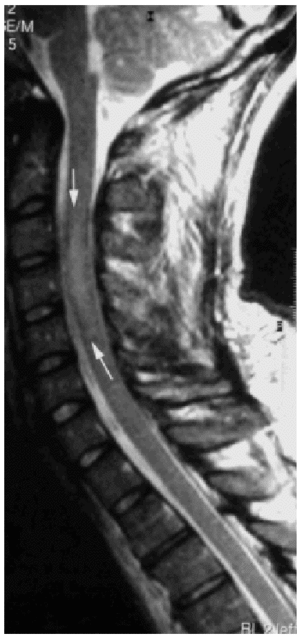

Se instaura tratamiento con una megadosis de corticoides. A las 12 h del ingreso se agrava la paresia en ESI (fuerza 2/3: movimiento activo eliminando la gravedad), con preservación sensitiva, por lo que se lleva a cabo una resonancia magnética nuclear que objetiva una contusión medular cervical que compromete los segmentos C3-C5.